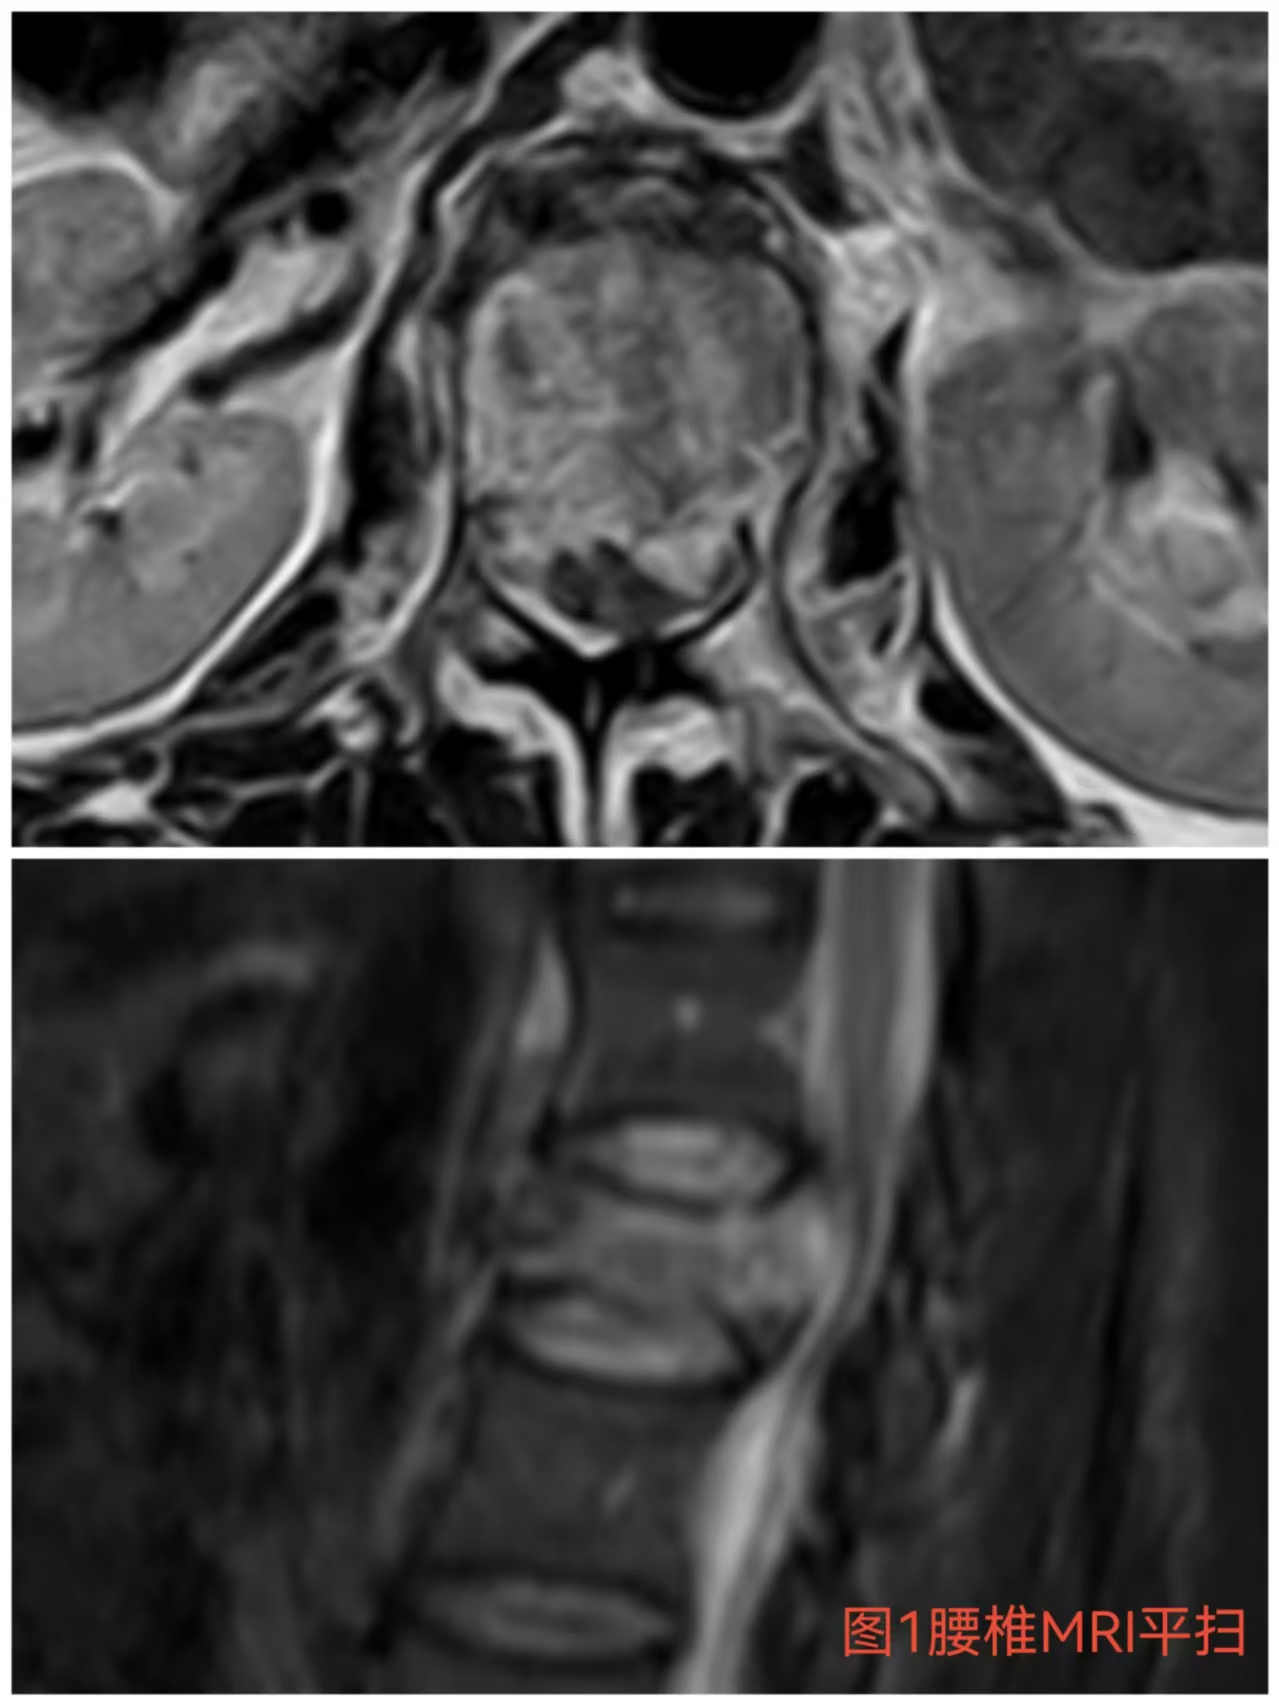

入院時患者躺在床上不能動彈,眼神中透漏著深深的無助,對于她來說這種傷情無疑是沉重的,尤其是腹股溝以下感覺消失、雙下肢肌力0級,這意味著其下肢無法活動及站立,仿佛被命運按下了暫停鍵;與病人及家屬充分溝通病情后,第一時間給予對癥治療,監(jiān)測患者生命體征,行腰椎核磁檢查(圖1)提示:腰1椎體爆裂性骨折,椎體后緣塌陷致骨性椎管狹窄,壓迫脊髓神經(jīng),結(jié)合患者病情及輔助檢查可診斷為:“L1椎體爆裂性骨折伴雙下肢截癱”。